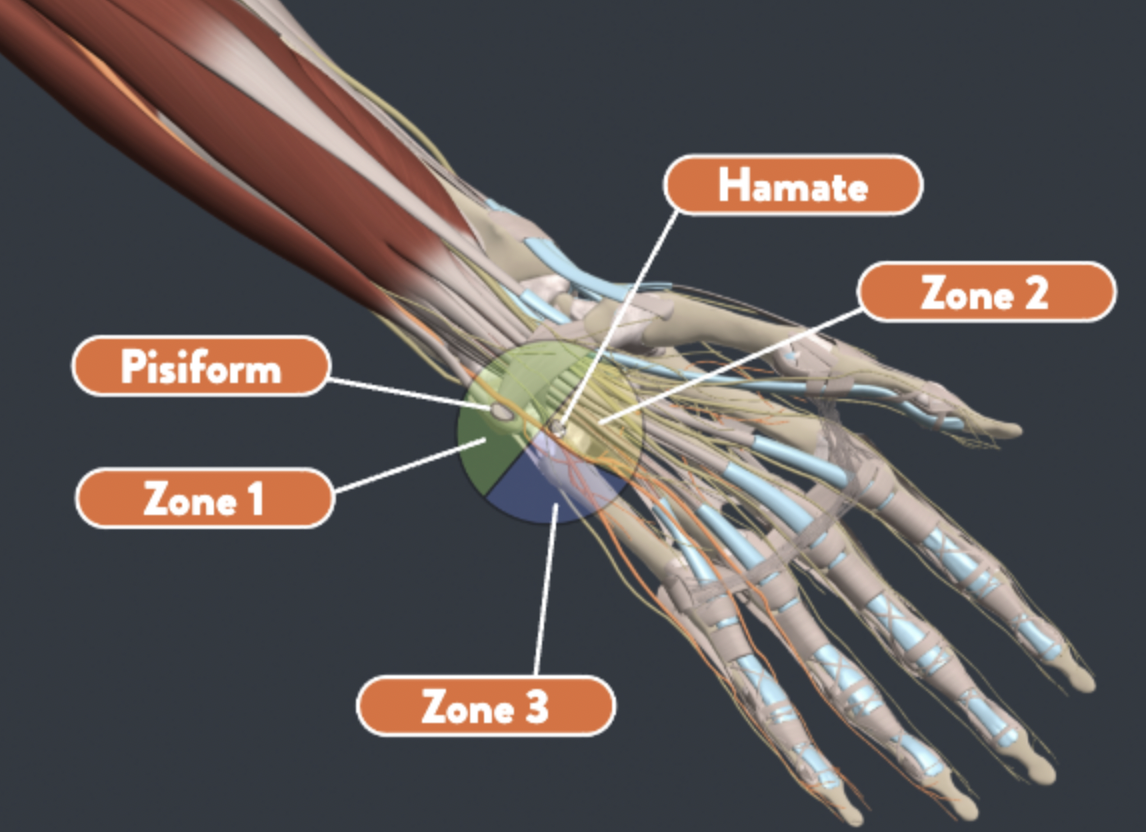

骑车人受伤:避免手部受伤和治疗策略

快速审查 Chiaramonte, R.、Pavone, P.、Musumeci, G.、Di Rosa, M. 和 Vecchio, M. (2022)。骑自行车者手部神经病变的预防策略、锻炼和康复:...